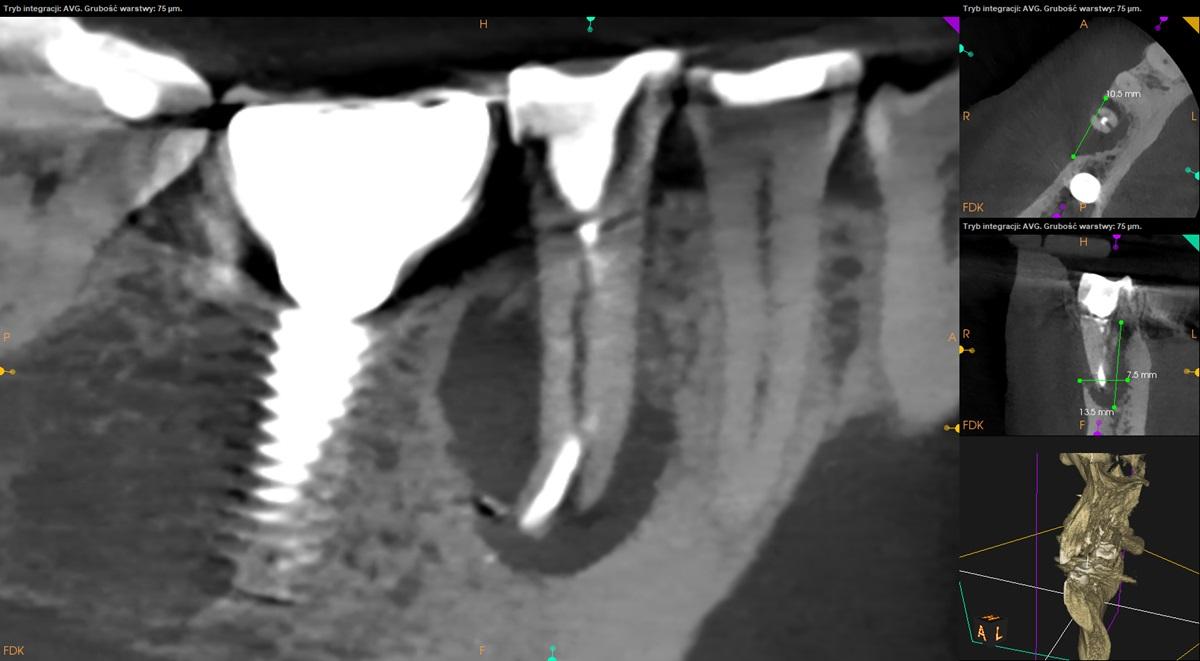

Tomografia szczęki i żuchwy, strona prawa.

Ząb 45 – po leczeniu kanałowym. Widoczne pionowe złamanie korzenia. Zanik tkanki kostnej wokoł korzenia obejmujący blaszkę zbitą po stronie przedsionkowej.